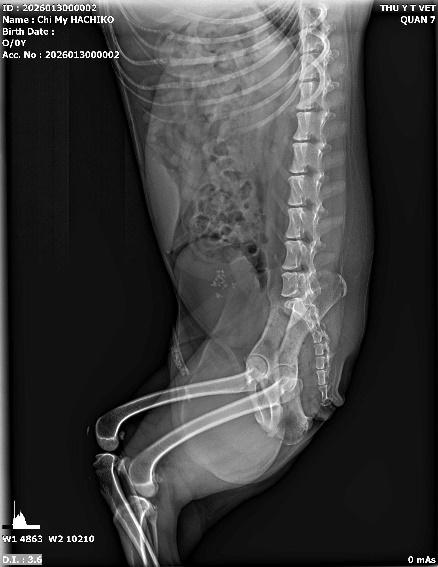

Đây là ứng dụng phổ biến nhất của X-quang. Từ những va chạm nhỏ đến các tai nạn giao thông nghiêm trọng, việc kiểm tra cấu trúc xương là bắt buộc. Dịch vụ X-quang giúp bác sĩ xác định:

• Vị trí gãy xương chính xác (xương đùi, xương chậu, xương trụ...).

• Kiểu gãy: Gãy cành tươi, gãy phức tạp, hay gãy hở.

• Độ lệch của các đầu xương để tiến hành phẫu thuật kết hợp xương (đóng đinh, bắt vít) hiệu quả nhất.

.jpeg)

Hình ảnh: chân vòng kiềng, ở các bé chân ngắn